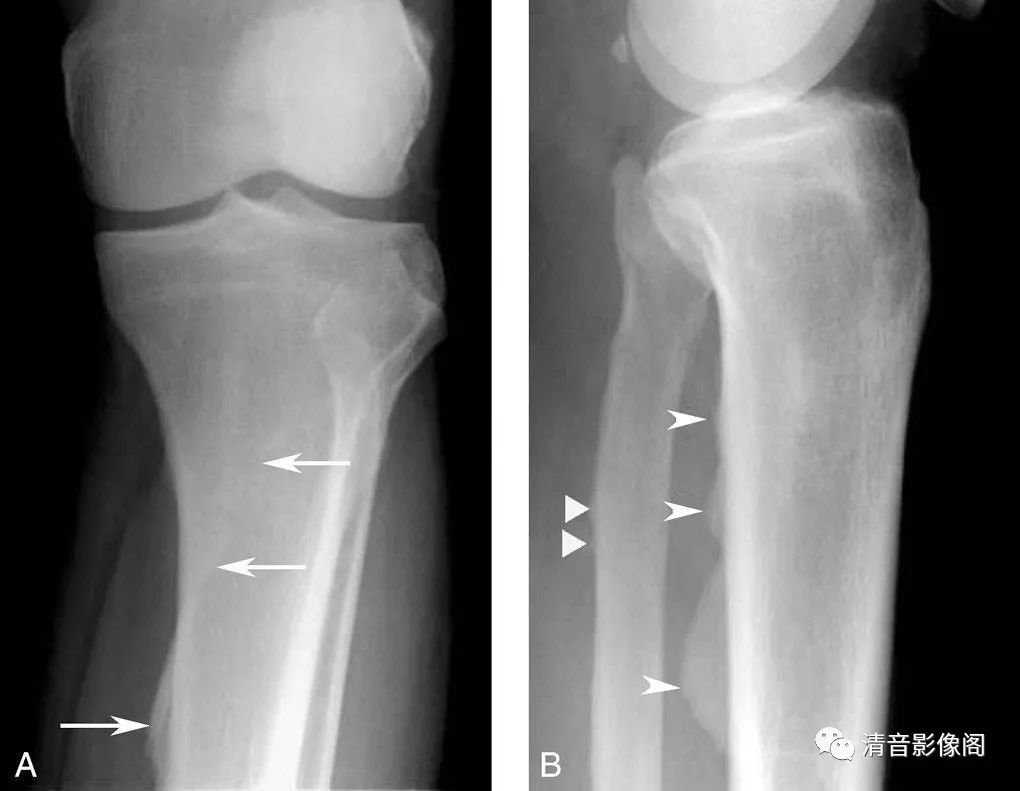

骨滋养管

A. 正位上胫骨上段可见纵行线样透亮影(箭),透亮线边缘有硬化缘,为滋养血管的投影,非裂隙性骨折;B. 侧位可见线样影从皮质的后上向前下走行,至骨髓内消失,不会穿越骨干(箭)。